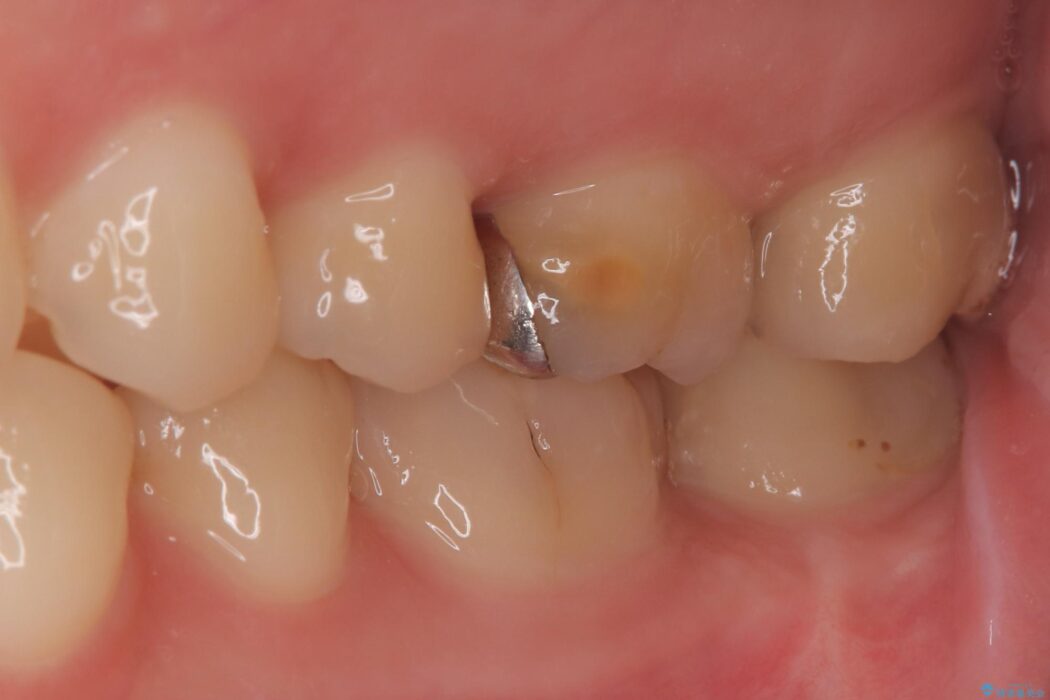

経過観察と土台作り: 一定期間の経過を観察し、痛みや炎症がないことを確認。神経の生存を確認した上で、セラミックを支えるための土台を精密に構築しました。

セラミックによる修復: 最終的な補綴物にはセラミックを使用しました。高い適合性により、二次的な虫歯のリスクを抑えつつ、天然歯のような自然な咬み心地と美しさを再現しました。